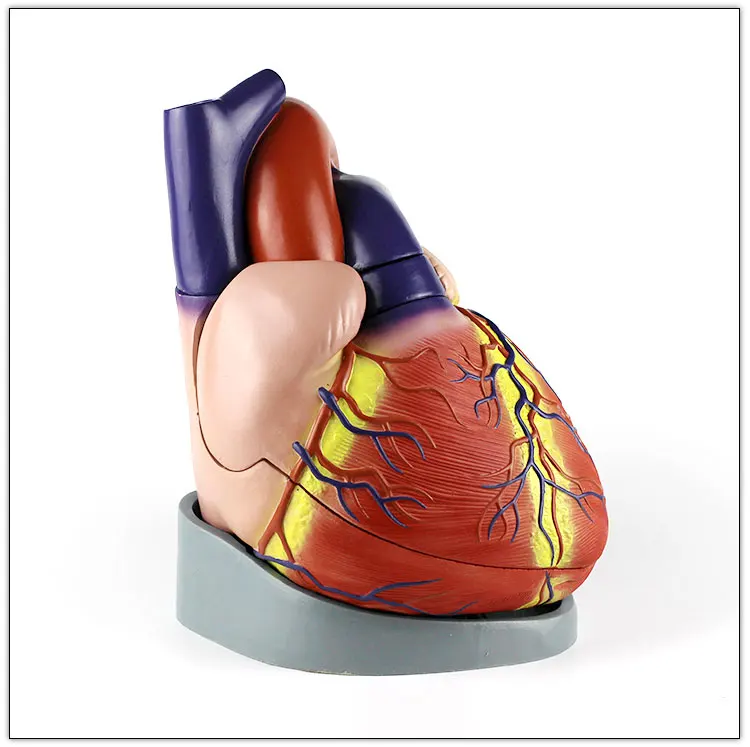

Valentine’s Day ช็อกโกแลตหัวใจ 12 ชิ้น – ของขวัญรังนกแท้ คอซซี่ โมเดลหัวใจมนุษย์ (Human Heart) | Shopee Thailand

โมเดลหัวใจมนุษย์ (Human Heart) | Shopee Thailand หัวใจมนุษย์ ภาพสต็อก – ดาวน์โหลดรูปภาพตอนนี้ – หัวใจ – อวัยวะภายใน …

ขยายกายวิภาคหัวใจมนุษย์รุ่น 3 ชิ้นส่วน – Buy กายวิภาคหัวใจ,หัวใจ … หัวใจมนุษย์ การออกแบบรายละเอียด ภาพประกอบสต็อก – ดาวน์โหลดรูปภาพตอนนี้ …

ชีวิตพลาสติกกายวิภาคหัวใจมนุษย์รุ่น2ชิ้นส่วน – Buy การสอนรุ่น,Anatomy … ช็อคโกแลตรูปหัวใจ [ภาพวาดฟรี] | OkusanPix

หัวใจวิทยาศาสตร์เรื่องกายวิภาคศาสตร์ทางการแพทย์หัวใจมนุษย์รุ่นขาย – Buy … รูปเวกเตอร์ฟรีหัวใจการ์ตูนปุ่ม PNG , หัวใจมนุษย์, หัวใจ, เซลล์ภาพ PNG …

ชีวิตพลาสติกกายวิภาคหัวใจมนุษย์รุ่น2ชิ้นส่วน – Buy การสอนรุ่น,Anatomy … ขนมช็อกโกแลตแท่ง ตรา โชกี้ โชกี้ 1 บาท แพ็ค 100 ชิ้น | Shopee Thailand

ขนมช็อกโกแลตแท่ง ตรา โชกี้ โชกี้ 1 บาท แพ็ค 100 ชิ้น | Shopee Thailand ชีวิตพลาสติกกายวิภาคหัวใจมนุษย์รุ่น2ชิ้นส่วน – Buy การสอนรุ่น,Anatomy …

ชีวิตพลาสติกกายวิภาคหัวใจมนุษย์รุ่น2ชิ้นส่วน – Buy การสอนรุ่น,Anatomy … รักสุดใจ! ช่อช็อกโกแลตให้เธอ รวมไอเดียช่อช็อกโกแลตสื่อรัก มอบให้แฟน

รักสุดใจ! ช่อช็อกโกแลตให้เธอ รวมไอเดียช่อช็อกโกแลตสื่อรัก มอบให้แฟน แบบจำลองหัวใจมนุษย์ขนาดชีวิตที่มีสีพื้นโปร่งใสโรคหัวใจทางการแพทย์แบบ …

แบบจำลองหัวใจมนุษย์ขนาดชีวิตที่มีสีพื้นโปร่งใสโรคหัวใจทางการแพทย์แบบ … Chocolate Heart, Hand-drawn sketch Chocolate s, brown, food png | PNGEgg

Chocolate Heart, Hand-drawn sketch Chocolate s, brown, food png | PNGEgg แบบจำลองหัวใจมนุษย์ขนาดชีวิตที่มีสีพื้นโปร่งใสโรคหัวใจทางการแพทย์แบบ …

แบบจำลองหัวใจมนุษย์ขนาดชีวิตที่มีสีพื้นโปร่งใสโรคหัวใจทางการแพทย์แบบ … ช็อกโกแลต รูปฟุตบอล เหรียญทอง หัวใจ บรรจุ 60 ชิ้น | Shopee Thailand

In-306 3d กายวิภาคศาสตร์หัวใจมนุษย์รูปแบบทางการแพทย์พลาสติกกายวิภาค … หัวใจมนุษย์ ภาพสต็อก – ดาวน์โหลดรูปภาพตอนนี้ – หัวใจ – อวัยวะภายใน, การ …

หัวใจวิทยาศาสตร์เรื่องกายวิภาคศาสตร์ทางการแพทย์หัวใจมนุษย์รุ่นขาย – Buy … หัวใจวิทยาศาสตร์เรื่องกายวิภาคศาสตร์ทางการแพทย์หัวใจมนุษย์รุ่นขาย – Buy …

หัวใจวิทยาศาสตร์เรื่องกายวิภาคศาสตร์ทางการแพทย์หัวใจมนุษย์รุ่นขาย – Buy … Anatomy หัวใจมนุษย์รุ่นพลาสติกทางการแพทย์กายวิภาคหัวใจจัมโบ้รุ่นอวัยวะ …

Anatomy หัวใจมนุษย์รุ่นพลาสติกทางการแพทย์กายวิภาคหัวใจจัมโบ้รุ่นอวัยวะ … รูปช็อกโกแลตหัวใจพร้อมน้ำเชื่อม PNG , วาเลนไทน์วัน, หัวใจ, วันแห่งความ …

3d Anatomy หัวใจมนุษย์รุ่นพลาสติกทางการแพทย์กายวิภาคหัวใจจัมโบ้รุ่น … หัวใจวิทยาศาสตร์เรื่องกายวิภาคศาสตร์ทางการแพทย์หัวใจมนุษย์รุ่นขาย – Buy …

หัวใจวิทยาศาสตร์เรื่องกายวิภาคศาสตร์ทางการแพทย์หัวใจมนุษย์รุ่นขาย – Buy … ส่งไว🚀24ชม. เจบีช็อกโกแลต รูปฟุตบอล เหรียญทอง เหรียญเงิน ทองแท่ง หัวใจ …

ส่งไว🚀24ชม. เจบีช็อกโกแลต รูปฟุตบอล เหรียญทอง เหรียญเงิน ทองแท่ง หัวใจ … Anatomy หัวใจมนุษย์รุ่นพลาสติกทางการแพทย์กายวิภาคหัวใจจัมโบ้รุ่นอวัยวะ …

Anatomy หัวใจมนุษย์รุ่นพลาสติกทางการแพทย์กายวิภาคหัวใจจัมโบ้รุ่นอวัยวะ … ภาพประกอบแบนเวกเตอร์หัวใจมนุษย์ขนาดใหญ่บนพื้นหลังสีขาว ภาพประกอบสต็อก …

หัวใจมนุษย์กายวิภาครุ่นวิทยาศาสตร์การแพทย์รูปแบบการสอน ห้องหัวใจมนุษย์: คำอธิบายโครงสร้างหน้าที่และประเภท

หุ่นจำลองหัวใจมนุษย์ 3d มนุษย์กายวิภาครุ่นหัวใจมนุษย์สำหรับซัพพลายเออร์แบบครบวงจรวิทยาศาสตร์ …

3d มนุษย์กายวิภาครุ่นหัวใจมนุษย์สำหรับซัพพลายเออร์แบบครบวงจรวิทยาศาสตร์ … 3d Anatomy หัวใจมนุษย์รุ่นพลาสติกทางการแพทย์กายวิภาคหัวใจจัมโบ้รุ่น …

3d Anatomy หัวใจมนุษย์รุ่นพลาสติกทางการแพทย์กายวิภาคหัวใจจัมโบ้รุ่น … อวัยวะหัวใจของมนุษย์ | องค์ประกอบกราฟฟิก แบบ PSD ดาวน์โหลดฟรี – Pikbest

รูปไอคอนเวกเตอร์มนุษย์หัวใจ PNG , การ์ตูน, หัวใจ, มนุษย์ภาพ PNG และ … หัวใจมนุษย์กายวิภาครุ่นวิทยาศาสตร์การแพทย์รูปแบบการสอน

หัวใจมนุษย์กายวิภาครุ่นวิทยาศาสตร์การแพทย์รูปแบบการสอน 15 Porch ช็อกโกแลต Fudge แม่พิมพ์ซิลิโคนหัวใจรูปเค้กช็อกโกแลตตกแต่ง DIY …

อุปกรณ์การศึกษากายวิภาคศาสตร์รุ่นหัวใจมนุษย์รุ่นสำหรับโรงเรียนขนาดชีวิต … วิธีทำ “นามะช็อกโกแลต” ของฝากยอดฮิตจากญี่ปุ่น อร่อยหรูดูแพง แต่ทำง่าย …